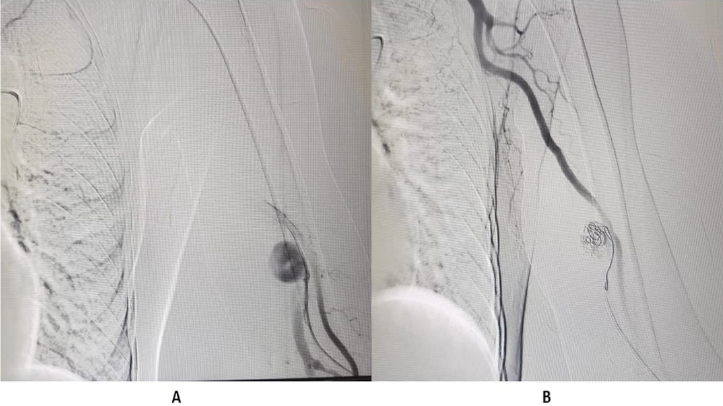

If right IJV is thrombosed, then IR accesses right External Jugular vein (EJV). If right side neck veins are thrombosed, then IR accesses left side neck veins: IJV or EJV (Figure 2). These tunnelled CVC are usually of size 14.5 French, with length 19, 23 or 27 cm, depending on patient’s height and from which side, neck vein is to be accessed. The cuff of tunnelled CVC is believed to prevent transmission of infection and also helps in securing CVC. If properly taken care of, then these tunnelled CVC can be used for 6-12 months. IR helps in managing these tunelled CVC, if flow rate is slow, by repositioning these CVC (Figure 3). IR have important role to play in managing AVF with slow flow rates. Most of times, stenosis is seen in these AVF, near anastomotic site. These juxta anastomotic AVF can be managed by IR by Percutaneous Transluminal Angioplasty (PTA), using appropriate size balloon. Some AVF show aneurysmal formation on venous side and these aneurysms can be managed successfully by IR (Figure 4). Sometimes, steal syndrome can be seen in AVF, due to reversal of flow in artery distal to anastomotic site. In case of steal syndrome, IR can block venous side using coils, in case of side to end AVF. This will increase flow rate in distal artery and reduce flow in fistula. In case of side-to-side AVF with steal syndrome, IR can successfully divert blood flow towards distal artery, by blocking collateral draining vein, distal to side-to-side anastomosis (Figure 5). If there is evidence of central vein stenosis, then IR can do PTA of central vein (Figure 6). If there is evidence of elastic recoil, with residual stenosis more than 30%, then IR can manage central vein stenosis by using metallic stent (Figure 7). Herein, it is important to stress upon Doppler and Spectral waveform, which helps IR to manage these dialysis fistula and graft [3-5]. In mature fistula and graft, inflow artery shows monophasic flow, with raised Peak systolic velocity (PSV) and End Diastolic velocity (EDV), with spectral broadening (Figure 8). In artery distal to anastomotic site, biphasic or triphasic waveform may be seen. On venous side, spectral waveform shows monophasic flow with turbulent arterial waveform (Figure 9).

Figure 4:

A. Pseudoaneurysm in draining left brachial vein.

B. Embolization of pseudoaneurysm done using interlock coil.